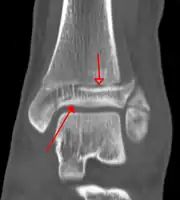

A triplane fracture of the ankle as seen on plain X-ray -

A triplane fracture of the ankle as seen on CT -

A triplane fracture of the ankle as seen on CT

On X-rays, there can be a fracture of the medial malleolus, the lateral malleolus, or of the anterior/posterior margin of the distal tibia. [17] If both the lateral and medial malleoli are broken, this is called a bimalleolar fracture[18]. If the posterior malleolus is also fractured, this is called a trimalleolar fracture. [19]